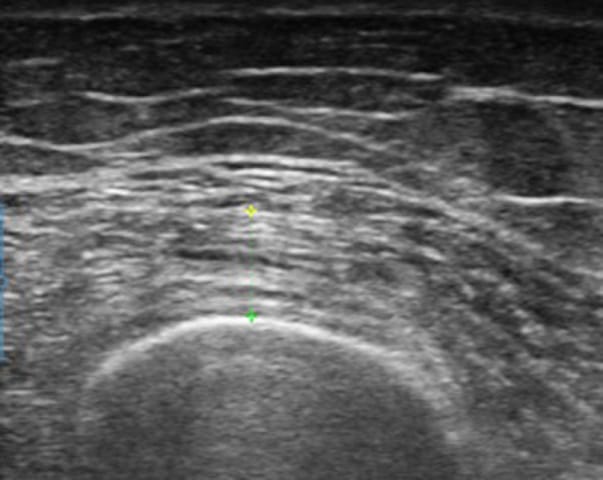

Échographie Intérêt de l'échographie musculaire respiratoire et périphérique dans l'évaluation de la tolérance à l'effort chez le sujet atteint d'obésité